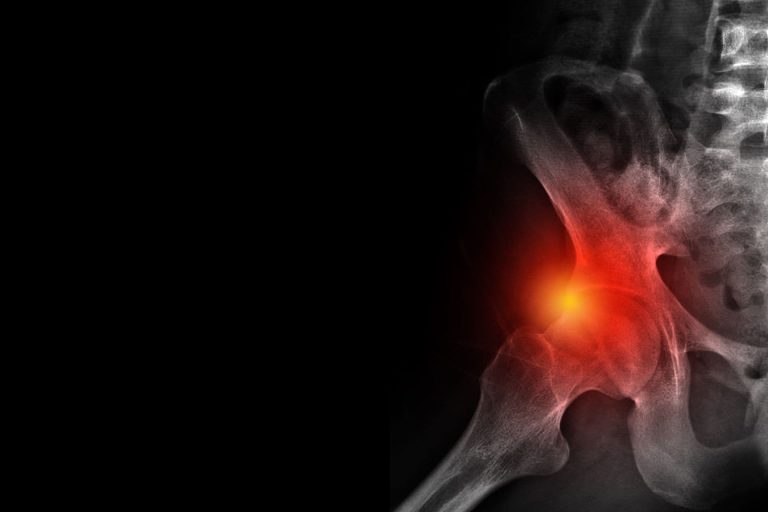

A csípőfájdalom tünetei, okai és kezelési lehetőségei

A csípőfájdalom alaposan megnehezítheti a mindennapokat, a kezeletlen probléma pedig akár súlyos szövődmények kialakulásához is vezethet. Milyen betegségek okozhatnak csípőfájdalmat, és melyek a leghatékonyabb kezelési módszerek a panaszok megszüntetéséhez? Alábbi cikkünkben részletesen válaszolunk! Milyen tünetekkel járhat a csípőfájdalom? A csípőfájdalom…

Femur acetabulum szindróma – a csípő ütközéses szindrómája

Az elmúlt időszakban egyre több olyan pácienssel találkozunk, akinek elülső csípő fájdalmának hátterében Femur Acetabulum Impingement (FAI), azaz Csípő Ütközési szindróma áll. A probléma lényege a csípő alaktani elváltozása, melynek következtében a combcsont nyaka, a mozgások (főleg flexió – hajlítás,…